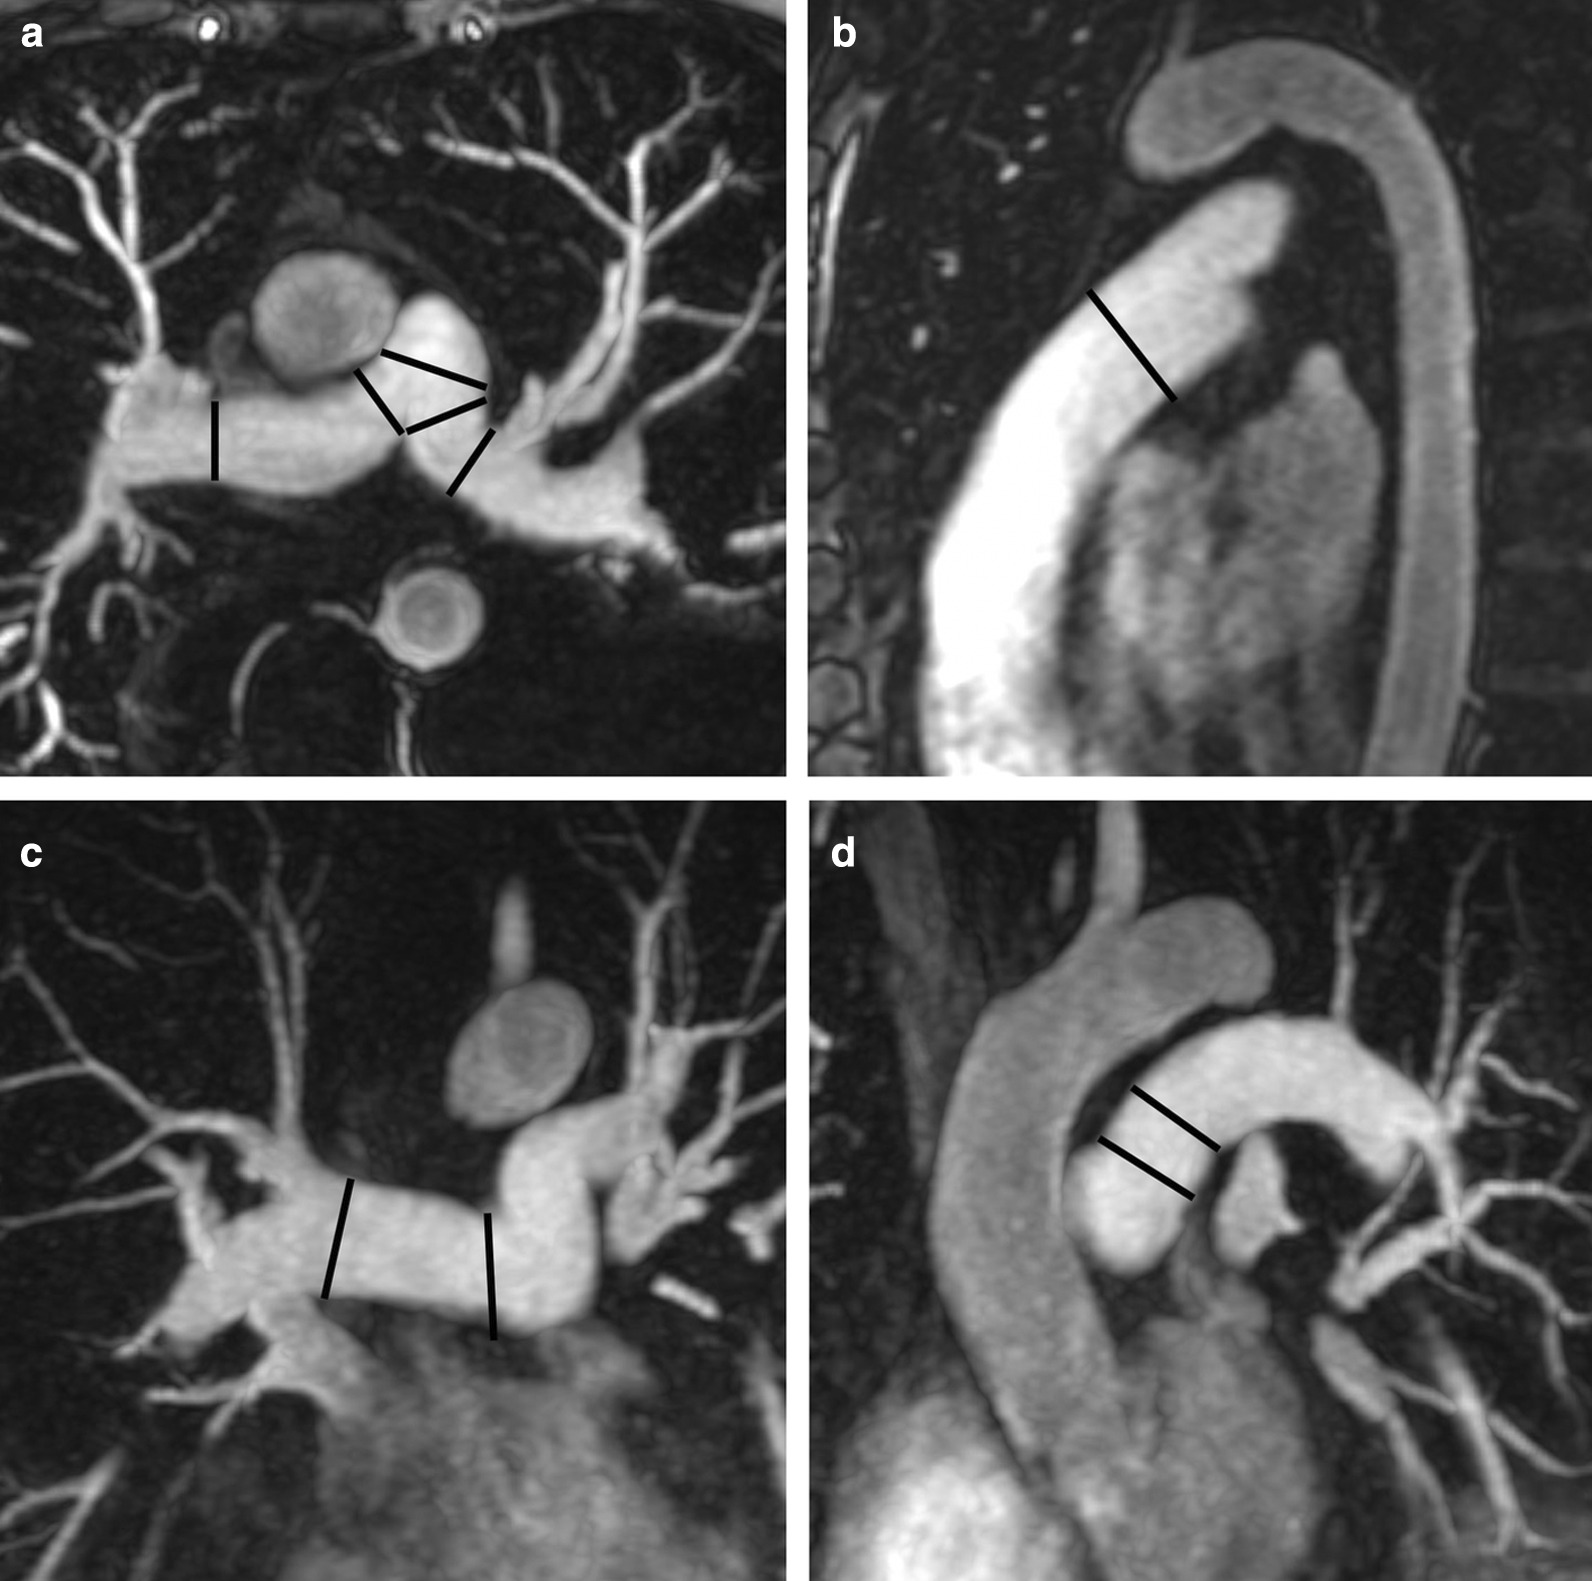

Measurements of LV diameter obtained on cine bSSFP images at diastole and systole on a 4 chamber view and short axis view are shown in Fig. 2.

Fig. 2.

Measurements of LV diameters obtained on cine bSSFP images during diastole (a, b) and systole (c, d) on the 4 chamber view (a, c) and short axis view (b, d). The longitudinal diameter of the LV was measured on the 4 chamber view as the distance between the mitral valve plane and the LV apex (a, c). On the 4 chamber view the transverse diameter was defined as the distance between the septum and the lateral wall at the basal level [18]. On the short axis view the transverse diameter was obtained at the level of the basal papillary muscles (b, d) [15]